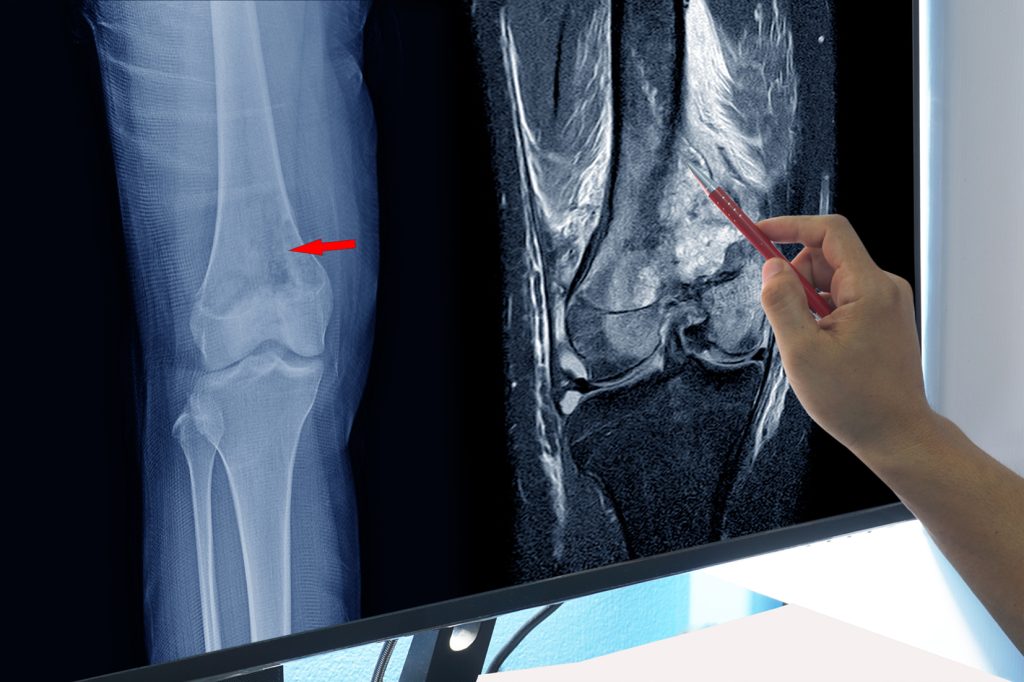

Posebno zabrinjavaju situacije u kojima dolazi do preloma kostiju bez značajne povrede. Takvi slučajevi mogu ukazivati na oslabljenu strukturu kostiju i zahtijevaju hitnu medicinsku procjenu. Ignorisanje ovakvih znakova može dovesti do širenja bolesti i komplikacija koje je teže liječiti.

Važno je razumjeti i razliku između različitih oblika bolesti. Postoje slučajevi kada problem nastaje direktno u kostima, ali i situacije kada se bolest širi iz drugih dijelova tijela. Ovakvi sekundarni oblici često su češći i mogu dodatno otežati postavljanje tačne dijagnoze. To znači da simptomi ne treba posmatrati izolovano, već u širem kontekstu cjelokupnog zdravlja.

U pozadini ovakvih stanja nalaze se promjene na nivou ćelija. Kada dođe do poremećaja u njihovom normalnom funkcionisanju, ćelije počinju da se nekontrolisano dijele, stvarajući masu koja može oštetiti zdravo tkivo. Ovaj proces često se razvija tiho, bez jasnih simptoma u ranoj fazi. Zbog toga je rana detekcija ključna za uspješnije liječenje i bolju prognozu.